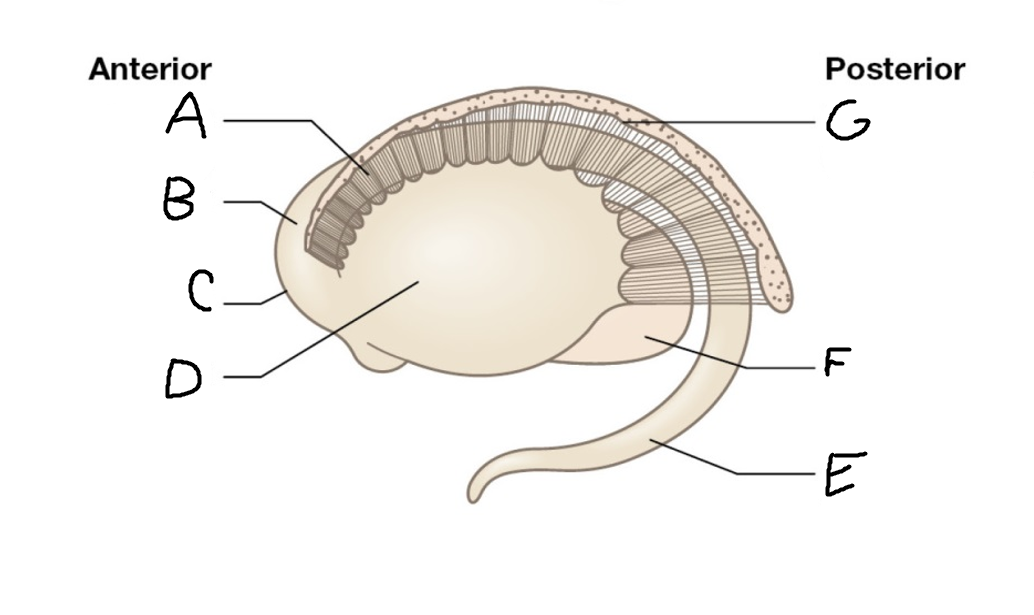

A

caudate nucleus head

C

caudate tail

D

globus pallidus (internal segment)

E

globus pallidus (external segment)

F

putamen